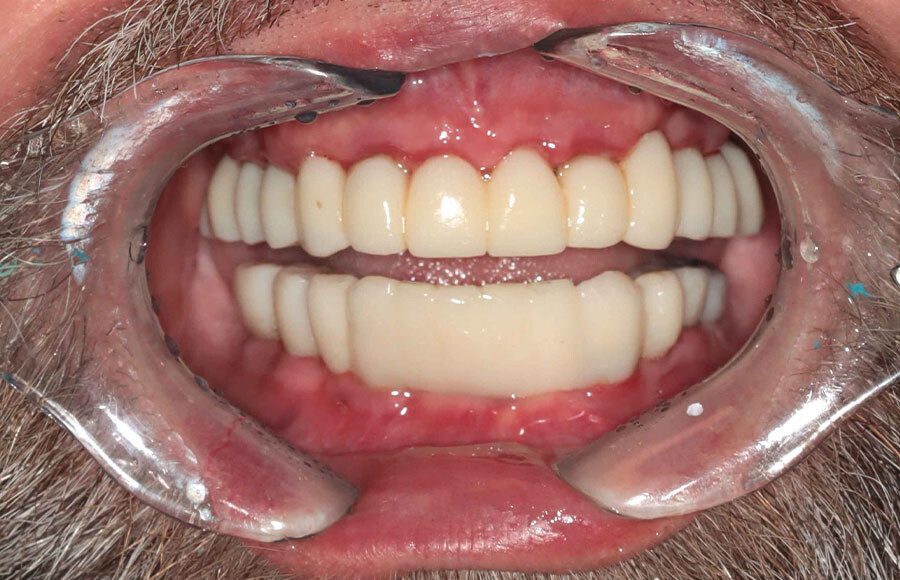

Patient wanted to see what longer, prettier teeth would look like. Crown preparations to prepare for crown lengthening and temporary crowns/bridge.

Three months later the patient returns for a series of appointments to fabricate his final prostheses. This is when we note that his homecare is slipping. Notice the redness at the gums that wasn’t seen previously. He was alerted to the issue and educated on how to improve.

Final prostheses, intraoral, frontal. Homecare is still a problem. The final restorations are much kinder to the tissues and we hope this will resolve some of the inflammation.